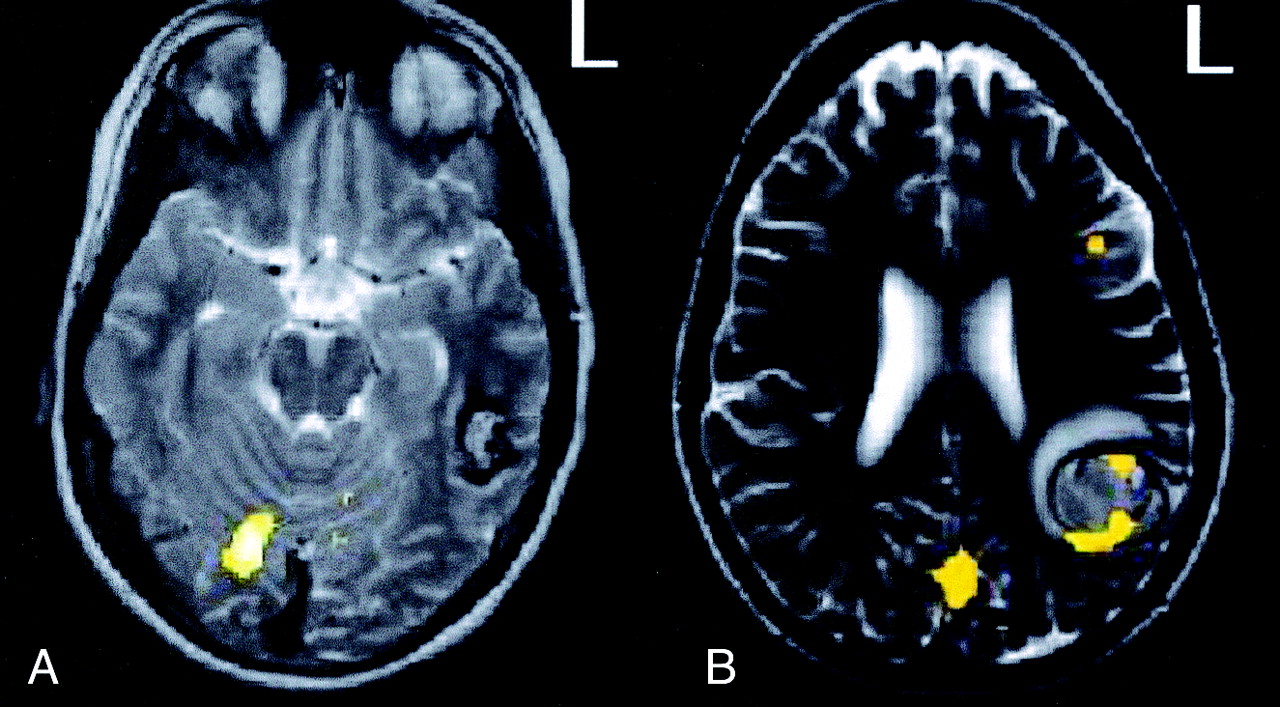

Patient contrasts.

A, Case 1. Sentence completion − letter string.

B, Case 2. Sentence completion − letter string.

Case 1.— A right-handed 16-year-old male adolescent who presented with seizures underwent a CT and subsequent MR revealing a cavernous angioma in the left posterior temporal lobe. The patient had been receiving antiepileptic medications. fMRI during the sentence-comprehension task results showed no activation in and around the lesion. Activation with sentence-completion − letter string suggested that the angioma posteriorly displaced a region involved in reading (Fig 2A). The glass brain in Fig 2A shows that sentence completion − letter string produced bilateral activation of the temporal lobes, as well as extensive frontal activation.

Results of the battery of language tasks were reported to the neurosurgical team. Frameless stereotactic surgery was performed, and the cavernous angioma was excised. Nine months after the surgery, an interview of the patient elicited no evidence of seizure activity. The patient had no deficits in his visual fields or difficulty reading or performing his schoolwork.

Case 2.—A 26-year-old right-handed woman had epilepsy caused by a cavernous angioma in the left inferior parietal region. The patient was taking various antiepileptic medications. Fig 2B shows the results with sentence completion − letter string. The glass brain in Fig 2B shows only left temporal activation and little frontal activation for sentence comprehension. Unlike the previous patient (Fig 3A), this patient had left-lateralized clusters of activation in and around the area of the cavernous angioma (Fig 3B).

Activation with sentence completion − letter string. Image for case 1 (A) shows no area of activation around the cavernous angioma, whereas that for case 2 (B) shows clear involvement.

Several days after the fMRI procedure, the patient had hemorrhage and underwent emergency surgery for evacuation of the hematoma and resection of the cavernous angioma. After surgery, she had anomia, mild alexia, and agraphia. Two weeks after the operation, she was admitted to the emergency department with Wernicke aphasia. Imaging revealed no new hemorrhaging, but EEG showed partial status epilepticus. Three years after surgery, she continued to have mild deficits, especially in complex reading.